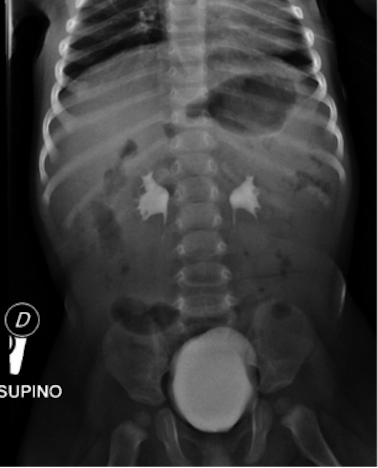

Nel sospetto di una patologia a carico del sistema nervoso centrale (SNC) venivano eseguite TC encefalo con mezzo di contrasto, risultata negativa per masse cerebrali espansive o alterazioni strutturali organiche, e rachicentesi, con fuoriuscita di liquor limpido. Veniva quindi avviata antibioticoterapia empirica ad ampio spettro con ceftriaxone. Allecografia-FAST eseguita in PS si riscontrava una falda di versamento libero in addome. In virtù di questultimo dato, del persistente stato soporoso e delletà del paziente, per escludere patologie addominali acute di pertinenza chirurgica veniva effettuato approfondimento radiologico in primis tramite RX addome (Figura 1), risultato poco dirimente se non per la presenza di alcuni livelli idroaerei nel tenue.